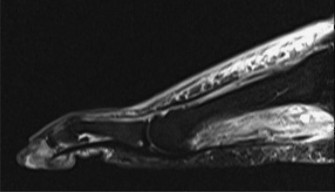

تشخيص تقلص عضلة الساق الخلفية

يعتمد تشخيص تقلص عضلة الساق الخلفية وقرح القدم على تقييم شامل يشمل التاريخ المرضي والفحص السريري الدقيق، بالإضافة إلى بعض الفحوصات التصويرية عند الحاجة. في عيادة الأستاذ الدكتور محمد هطيف في صنعاء، يتم اتباع نهج متكامل لضمان تشخيص دقيق يمهد الطريق لخطة علاجية فعالة.

الفحص البدني الدقيق:

- تقييم الأوعية الدموية: جس النبض في القدم (الشريان الظهري للقدم، الشريان الظنبوبي الخلفي)، زمن إعادة امتلاء الشعيرات الدموية، درجة حرارة الجلد، وجود احمرار. قياس مؤشر الضغط الكاحلي العضدي (ABI) ومؤشر ضغط إصبع القدم العضدي (TBI) ضروريان. يوصى بشدة بقياس ضغط الأكسجين عبر الجلد (TcPO2)، خاصة لدى مرضى السكري، لتقييم حالة الدورة الدموية الدقيقة. إذا اشتبه في وجود قصور وعائي، فإن الإحالة لجراح الأوعية الدموية وإجراء فحوصات تصويرية (مثل تصوير الأوعية) أمر إلزامي.

- التقييم العصبي: اختبار خيوط سيمز-وينشتاين للإحساس الواقي، الإحساس بالاهتزاز (باستخدام شوكة رنانة 128 هرتز)، وخز الدبوس، اللمس الخفيف، الإحساس بالموضع. تقييم الوظيفة الحركية (عضلات القدم الداخلية، العضلات الباسطة والمثنية للكاحل).

الفحص العضلي الهيكلي:

- **اختبار سيلفرسكيولد (Silf